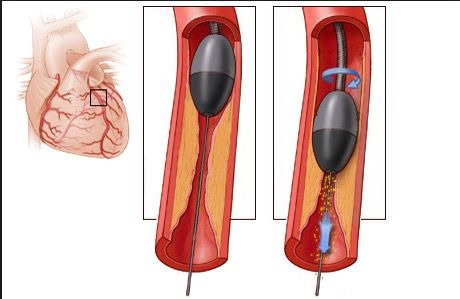

Rotablation, also known as Rotational Atherectomy, is an advanced technique used during angioplasty. It’s designed to treat heavily calcified and hardened coronary artery blockages that are resistant to standard balloon angioplasty.

This technique uses a high-speed rotating burr to grind down the plaque, making it easier to open the artery and place a stent.

• Rotablator Burr: A diamond-tipped burr rotates at speeds up to 200,000 RPM.

• Grinding the Plaque: It grinds the calcium into microscopic particles.